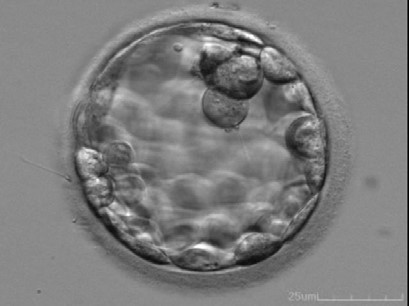

This Day-5 blastocyst is scored according to the Istanbul consensus workshop criteria as:

1.

blastocyst —-EXPANDED (3)

ICM few cells no compaction-poor (3)

TE fair (2)

= 3CB